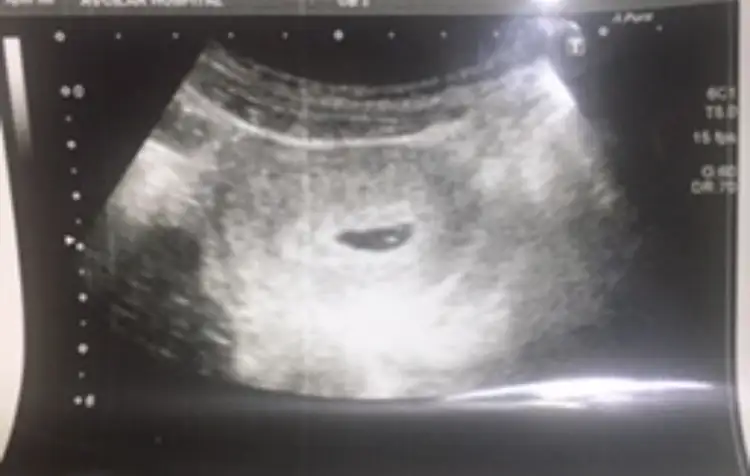

6-7 . haftalara ait ultrason görüntünüz eliniz de varsa inceleyin. Bebek sağ tarafta ya da sağ tarafa daha yakınsa kız , Eğer bebek sol tarafta ya da sol tarafa yakınsa cinsiyeti erkektir.